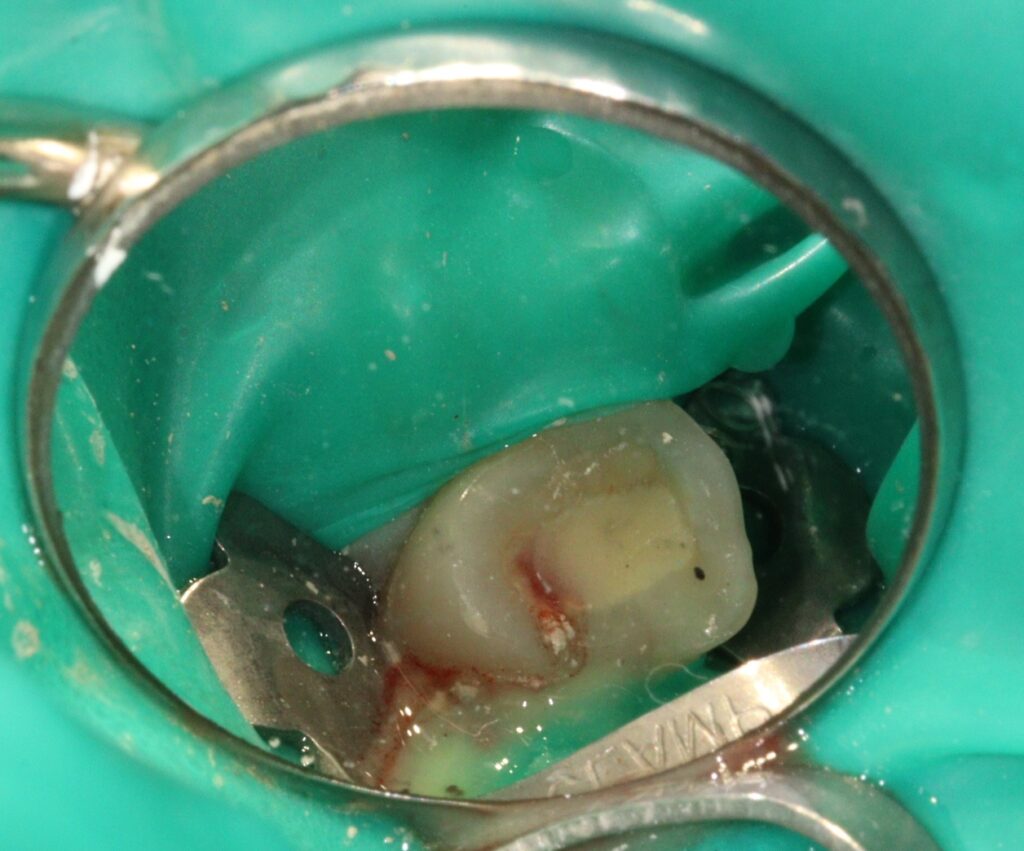

재신경치료의 과정입니다.

치료 시 근관 내 MTA 충전까지

함께 진행하였습니다.

MTA 는 미세한 틈까지 촘촘하게 메워주는

높은 밀봉력으로 세균 유입 가능성을 낮춰

염증의 재발을 줄이고

치아를 오랫동안 기능적으로

유지할 수 있도록 도와주는데요.

무엇보다도 MTA는 인체 친화적인 무기질 재료로

치수와 직접 접촉해도 자극이 적고

세포 재생을 유도하는 특징을 지니고 있습니다.

재신경치료는 기존의 근관 충전재를 제거하고

감염된 부위를 다시 소독한 뒤

정밀하게 재충전하는 과정을 거쳐야 하기 때문에

더 정교한 기술과 경험이 요구됩니다.